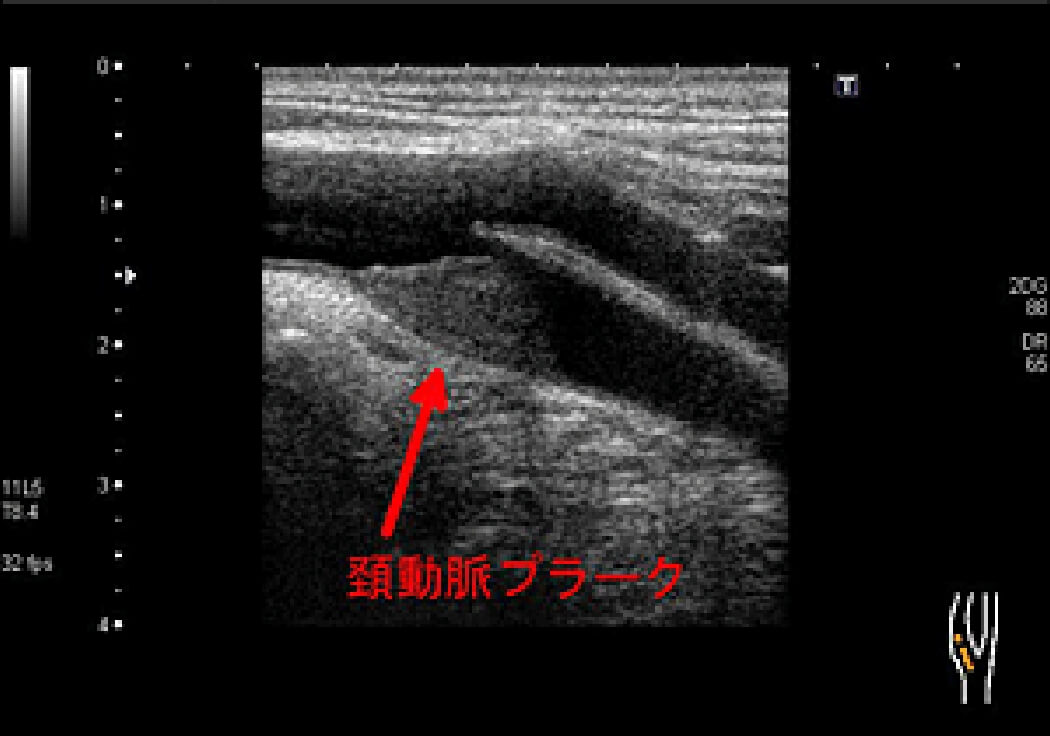

頸動脈における石灰化や狭窄状況、動脈硬化の指標の一つである内膜中膜複合体肥厚度(IMT)やプラークの有無等を調べる検査です。

頚動脈に狭窄や血栓、石灰化があると、脳や心臓にも動脈硬化がある可能性が高くなり、これらの梗塞のリスクが高くなっていることを示します。

頚動脈プラークの例